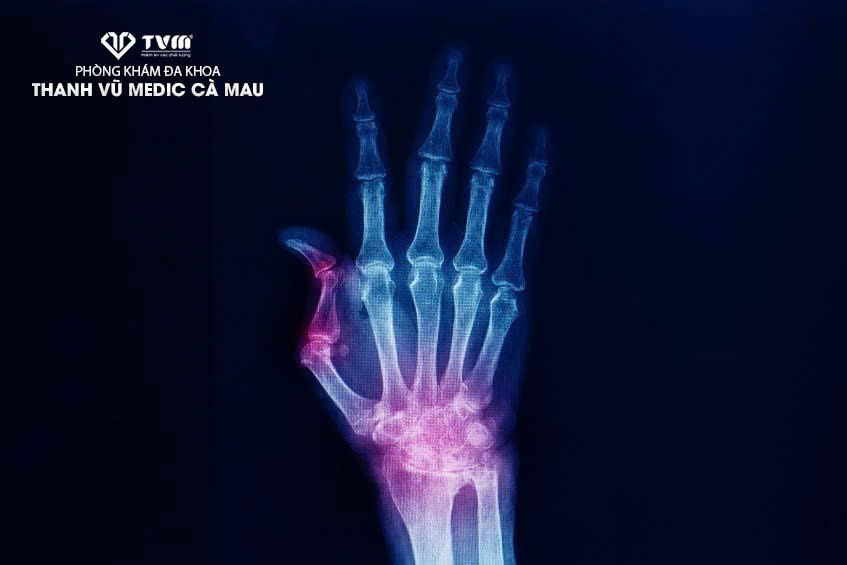

Viêm khớp ngón tay cái có thể gây ra các biểu hiện như đau, sưng khớp… Khi bị viêm khớp ngón tay cái, người bệnh cần được thăm khám và điều trị sớm. Vậy cần điều trị viêm ngón tay cái như thế nào?

Viêm khớp ngón tay cái (hay viêm ngón tay cái) là một dạng bệnh viêm xương khớp, xảy ra do bề mặt sụn khớp – khớp giữa nền xương bàn ngón tay cái và xương thang vùng cổ tay bị mài mòn hoặc trong tình trạng lão hóa. Viêm khớp ngón tay cái là loại viêm khớp phổ biến thứ hai ảnh hưởng đến bàn tay, chỉ đứng sau bệnh viêm khớp ngón tay nói chung. Tỷ lệ bị viêm khớp ngón tay cái ở nữ giới cao hơn so với nam giới, nhất là ở độ tuổi sau 40. (1)

Hình ảnh viêm khớp ngón tay cái

Viêm khớp ngón tay cái là một trong những dạng bệnh viêm khớp.

Viêm khớp ngón tay cái có thể gây biến dạng khớp